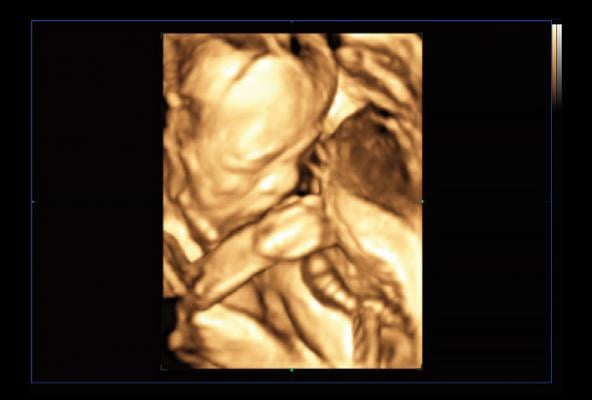

Using an Intel Core i3 processor, the Intel Distribution of OpenVINO toolkit and OpenCV toolkit, Samsung Medison’s BiometryAssist automates and simplifies fetal measurements, while LaborAssist automatically estimates the fetal angle of progression (AoP) during labor for a complete understanding of a patient’s birthing progress, without the need for invasive digital vaginal exams.

BiometryAssist automates and standardizes fetal measurements in approximately 85 milliseconds with a single click, providing over 97% accuracy. This allows doctors to spend more time talking with their patients while also standardizing fetal measurements, which have historically proved challenging to accurately provide. With BiometryAssist, physicians can quickly verify consistent measurements for high volumes of patients.

During labor, LaborAssist helps physicians estimate fetal AOP and head direction. This enables both the physician and patient to understand the fetal descent and labor process and determine the best method for delivery. There is always risk with delivery and a slowing progress could result in issues for the baby. Obtaining more accurate and real-time progression of labor can help physicians determine the best mode of delivery and potentially help reduce the number of unnecessary cesarean sections.

“LaborAssist provides automatic measurement of the angle of progression as well as information pertaining to fetal head direction and estimated head station. So it is useful for explaining to the patient and her family how the labor is progressing, using ultrasound images which show the change of head station during labor. It is expected to be of great assistance in the assessment of labor progression and decision-making for delivery,” said Professor Min Jeong Oh, M.D., Ph.D., Department of Obstetrics and Gynecology, Korea University Guro Hospital in Seoul, Korea.